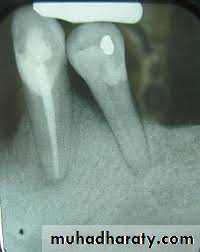

- Insufficient periodontal support:

Periodontal or periapical disease → alveolar bone loss →lack of periodontal support.

Inadequate crown - root ratio.